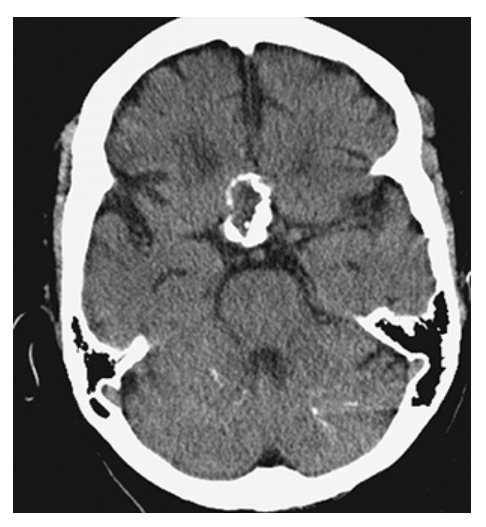

Ependymoma. Axial NECT shows a large mass with calcifications arising from the fourth ventricle and extending posteriorly. There is also hydrocephalus due to obstruction of cerebral spinal fluid (CSF) flow by the mass.